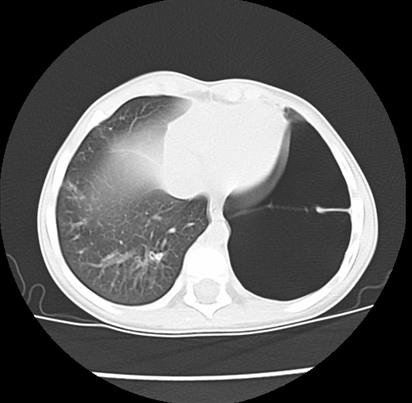

We asked for a Chest CT scan